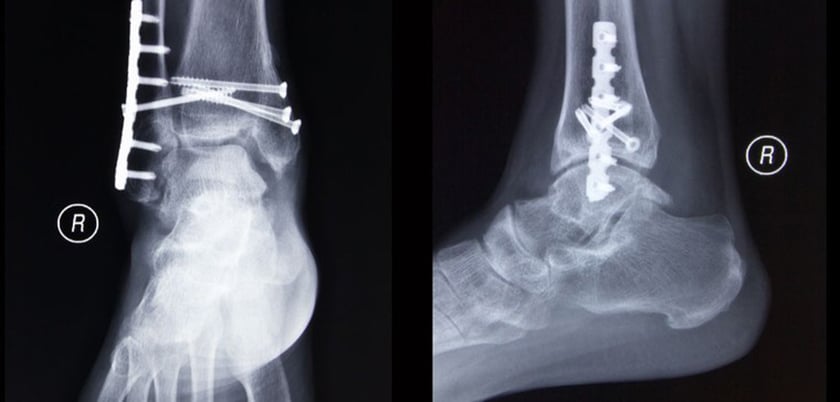

Until now, two techniques have been used to treat unstable fractures. People either received open surgery to set and then fix the bones using plates and screws, or they received a traditional plaster cast.

Professor Willett said: 'Each technique has drawbacks. Traditional plaster casts are associated with misaligned bones, poor healing and plaster sores. Surgery, especially in older people, is often complicated by poor implant fixation, wound healing problems and infection. However, a Cochrane review - considered a gold standard assessment of evidence for or against a medical technique or treatment - could not recommend preferring either treatment, as studies comparing them were of low quality.'